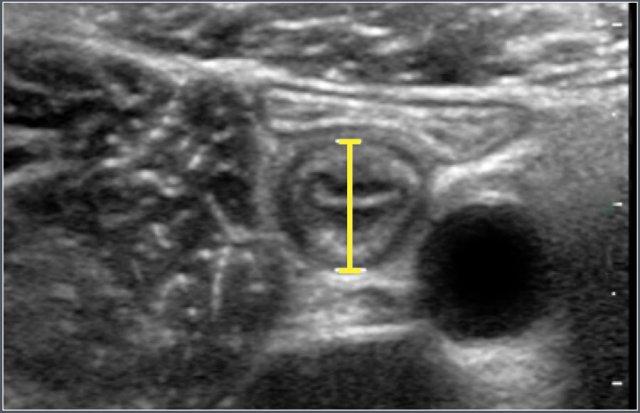

Độ dày thành ruột được đo trên các mặt cắt siêu âm theo trục ngang và bao gồm các lớp mô học sau: niêm mạc, lớp đệm niêm mạc, cơ niêm, dưới niêm mạc và cơ thành ruột.

Ví dụ siêu âm

Đo độ dày thành hồi tràng đoạn cuối ở bệnh nhân nam 12 tuổi mắc xơ nang.